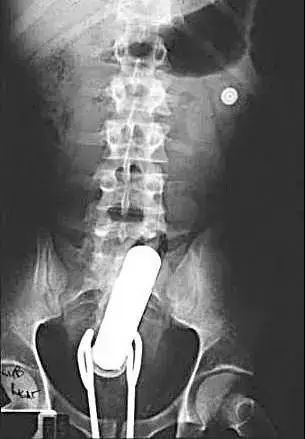

首先,医生会用指诊 、X线等等一系列的办法,来确定里面的异物是什么、在什么位置。这一点很关键,因为患者的描述可能很不清晰,甚至还会撒谎。而搞清楚里面真正的情况,这样才能找到合适的方法把它取出来。